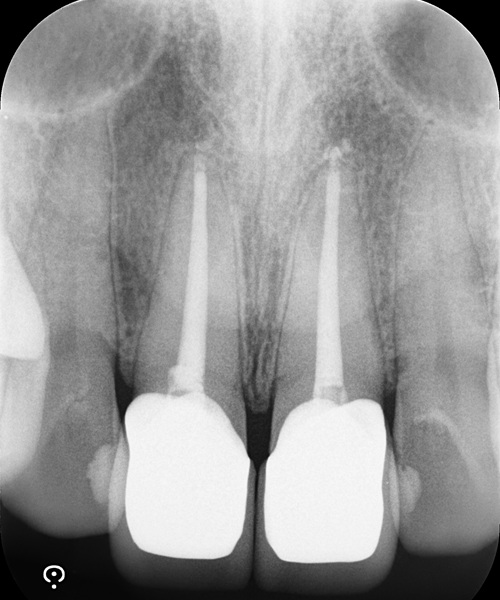

術後

| 治療名 | 精密根管治療と前歯セラミッククラウンによる審美修復症例 |

| 治療説明 |

以前に治療された前歯の被せ物の見た目を気にされ、再治療をご希望されました。 審美性だけでなく、内部の根管治療まで丁寧に行うことで、将来的なトラブルのリスクを抑えた、長期的に安定した治療結果を目指しました。 |

| 治療回数・期間 | 4回 |

| 副作用とリスク | ・保険診療の銀歯と比べて費用が高額になります。 ・根管治療からクラウン装着までを含めると、治療期間が長くなる傾向があります。 |

| 料金(税込) | 精密根管治療:88,000円×2本 セラミッククラウン:132,000円×2本 合計:440,000円(税込) |